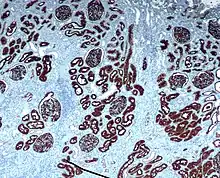

Immunochemistry

CD10 is used in clinical pathology for diagnostic purpose.

In lymphomas and leukemias

- Acute lymphoblastic leukemia (ALL) cells are CD10+.

- Follicular lymphoma (follicle centre cell lymphoma) are CD10+.

- Burkitt Lymphoma cells are CD10+.

- CD10+ diffuse large B cell lymphoma (CD10+ DLBCL)[20]

- Angioimmunoblastic T cell lymphoma (AITL) are CD10+[25][26] and distinguishes AITL from other T cell lymphomas (CD10−)[27]